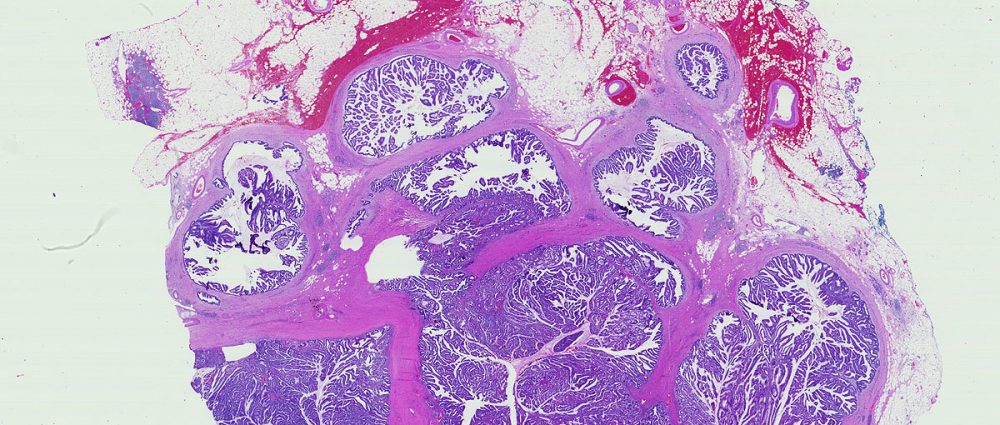

A term used to describe certain tumors which grow in finger-like projections. Pathologists use this term to describe some precancerous lesions in the pancreas (intraductal papillary mucinous neoplasm).

A fluid filled sac. Some tumors of the pancreas, including the serous cystadenomas and intraductal papillary mucinous neoplasms, form cysts. Cysts have a distinct appearance in CT scans. They are important to recognize because the treatment of cystic tumors can differ from that for solid tumors.